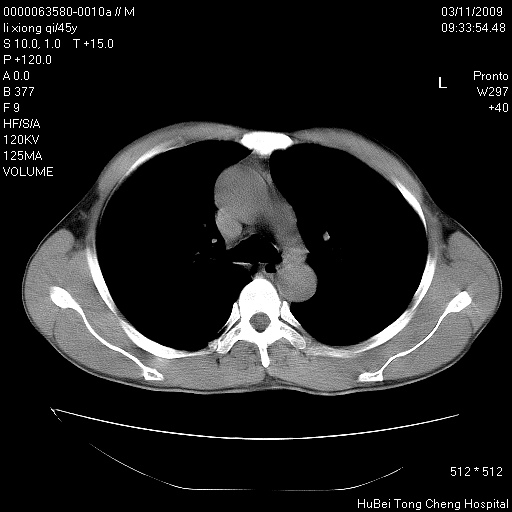

患者 男,45岁。胸痛,咳嗽伴痰中带血1月余。

临床诊断:肺结核?

胸部ct轴位平扫(层厚10mm,螺距1.5,重建间隔10mm),图像如下:

考虑肝癌肺转移

考虑肝癌肺转移。

肝癌肺转移